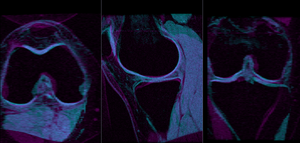

Slicer Registration Library Case #21: Align knee MRI of two different subjects

- for better visibility, you can change the colormaps of the two volumes, as used in the examples shown here. Switch to the Volumes module, select "MRI_58" and then select "Green" from the Lookup Table menu. Similarly select "Cyan" for "MRI_64".

- check the result

- Place "MRI_58" in the background and "MRI_64" in the foreground

- switch to the Data module, locate the "MRI_64" node, and drag it onto the newly created "Xf1_Affine" node.

- fade between background and foreground to judge the alignment.

- for better visibility, you can change the colormaps of the two volumes, as used in the examples shown here. Switch to the Volumes module, select "MRI_58" and then select "Green" from the Lookup Table menu. Similarly select "Cyan" for "MRI_64".

- check the result

- Place "MRI_58" in the background and "MRI_64_Xf3" in the foreground

Registration Results